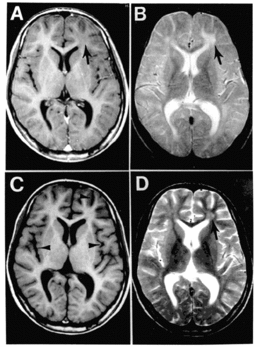

La PESS provoque une démyélinisation des neurones cérébraux et peut entraîner de nombreux handicaps[3],[4].